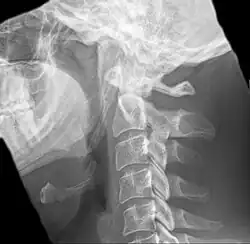

Radiograph, lateral view showing elongated stylohyoid process and stylohyoid ligament ossification

Imaging is important and is diagnostic. Visualizing the styloid process on a CT scan with 3D reconstruction is the suggested imaging technique.[13] The enlarged styloid may be visible on an orthopantogram or a lateral soft tissue X ray of the neck.